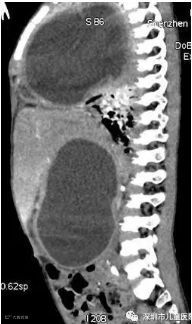

医生对他的肚子进行了CT检查,结果显示,京京右侧胸腔及右侧腹腔,各有一个巨型囊肿。

囊肿压迫了肺部,京京随时都会有生命危险,必须尽快处理掉。